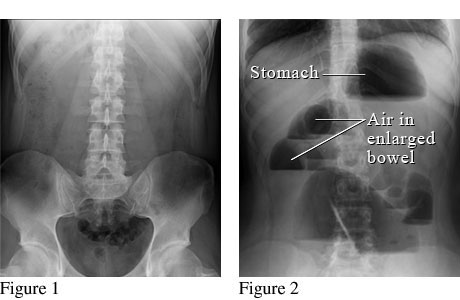

Abdominal X-Ray of a Bowel Obstruction

Figure 1 shows a normal abdomen. Figure 2 shows air trapped in the bowels because gas, fluids, or solids can't move through the bowels normally.